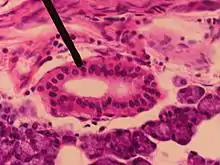

Sección de glándula submaxilar. Conducto semidiagramático. 200x.